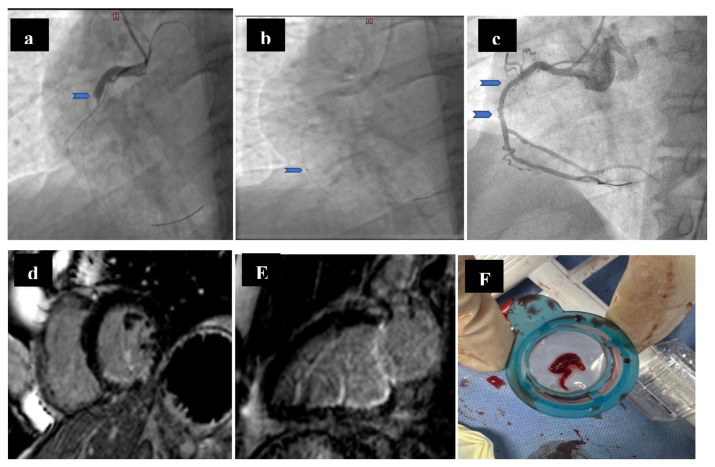

Methods: Ninety-three patients with heavy thrombus burden were enrolled in this study; sixty-five patients met our inclusion criteria. After failed trial of restore the artery patency, aspiration thrombectomy was done followed by PCI for thirty-one patients (aspiration group), while conventional PCI without aspiration thrombectomy was performed for 34 patients (conventional group). The primary end points were both occurrence and extent of microvascular obstruction (MVO) evaluated mainly by CMR, in addition to angiographic data (MBG and TIMI flow grade).

Results: The incidence of microvascular obstruction (MVO) was significantly higher in conventional group (18 patients, 52.9 %) when compared with aspiration group (7 patients, 22.6 %; p-value = 0.012). Moreover, significant differences existed between the studied groups regarding MVO extent. For instance, MVO extended to >4 segments in only 3 patients (9.7 %) in aspiration group, but in 13 patients in conventional group (38.2 %; p-value = 0.007).

Conclusions: Aspiration thrombectomy substantially reduces both the incidence and extent of microvascular obstruction as an adjunctive technique to PPCI in STEMI patients with heavy thrombus burden.